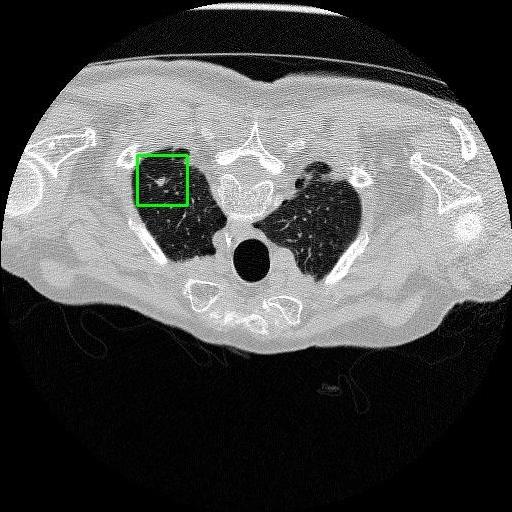

We developed an AI-based system using deep learning models for analyzing lung CT scans to detect and classify pulmonary nodules. We chose the YOLOv11 architecture for its enhanced object detection capability and adapted it specifically for medical imaging, incorporating pixel-level precision and severity classification.

Classification into three severity levels with colored bounding boxes.

Maintaining performance on small, complex features like micro-nodules tested the limits of traditional object detectors.

Designed a severity classification system that categorizes nodules into null, moderate, and severe using colored bounding boxes, assisting in rapid clinical decision-making.